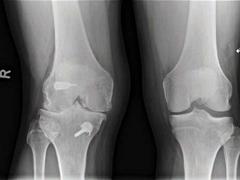

Letsels van de voorste kruisband (VKB) komen meestal voor bij pivoterende sporten zoals voetbal, hockey, korfbal en zaalsporten. Patiënten krijgen vaak het advies om de VKB te laten reconstrueren omdat ze anders slijtage van de knie krijgen. Het ontstaan van knie-artrose (gonartrose) na een VKB-ruptuur is echter een multifactorieel proces. Wetenschappelijk onderzoek toont aan dat het risico op röntgenologische artrose van de knie gelijk is bij patiënten met en zonder reconstructie van de VKB. De in de praktijk vaak gemaakte opmerking ‘U moet uw voorste kruisband laten reconstrueren, anders krijgt u slijtage van de knie’ is onjuist. Indicaties voor een VKB-reconstructie van de knie zijn klachten van invaliderende functionele instabiliteit, bij het hechten van een meniscusruptuur en de wens tot pivoterende (sport)activiteiten.